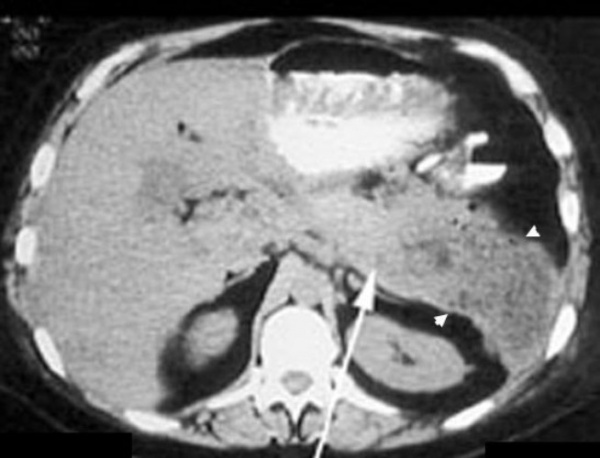

(Левый) На поперечном УЗ срезе в теле поджелудочной железы определяется псевдокиста несколько дольчатой формы с четкой капсулой и слоистым, оседающим под действием гравитации осадком. Обратите внимание, что псевдокиста смещает желудок кпереди.

(Правый) При КТ с контрастным усилением на аксиальной томограмме у того же пациента в теле поджелудочной железы определяется псевдокиста. Слоистый детрит на этой томограмме виден плохо, при УЗИ он определяется гораздо лучше.